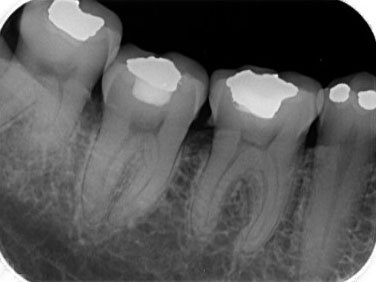

RX. Periapicales

RX. Bitewing